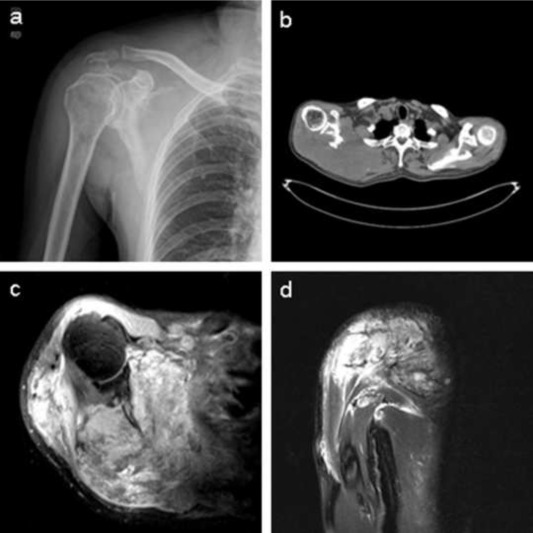

Laboratory tests showed that the serum concentration of CEA reached 17.64 ng/ml. Imaging: X-ray (Fig. 1 a) showed the destruction of the right scapula, and a shadow of soft tissue mass in right scapular region; CT (Fig. 1 b) showed right scapula destructed, surrounded by irregular low-density mass shadow. MRI (Fig. 1 c, d) showed a shadow of soft tissue mass inside of right shoulder, two rounded nodule below the right clavicle, considering as a malignant tumor of the right scapula, right subclavian lymph node metastasis. Emission computed tomography (ECT) showed high metabolism activity in the right scapula, right shoulder and right clavicle bone (Fig. 2 ). Preoperative needle biopsy report: clear cell sarcoma (Fig. 3 ); immunohistochemical staining: PCK (−), LCA (−), Melanoma (−), Syn (+), desmin (−), S-100 (+), CD68 (±), vimentin (+).

Fig. 1. (a), X-ray images show right scapula and that distal clavicle is destructed by tumor. (b), CT images show that right scapula is destructed and surrounded by irregular low-density mass shadow. (c), (d), MRI images show a shadow of soft tissue mass inside of right shoulder and two subclavian lymph nodes metastasis sites. |